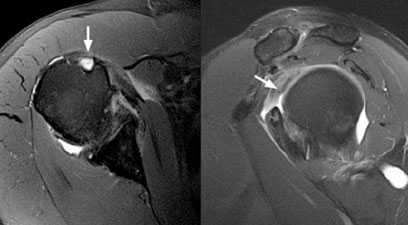

Рис.3 МРТ-картина разрыва сухожилия длинной головки бицепса

На МРТ диагноз отрыва дистального сухожилия двуглавой мышцы плеча был подтверждён. На представленных выше снимках отчётливо визуализируется оторванное сухожилие двуглавой мышцы плеча.